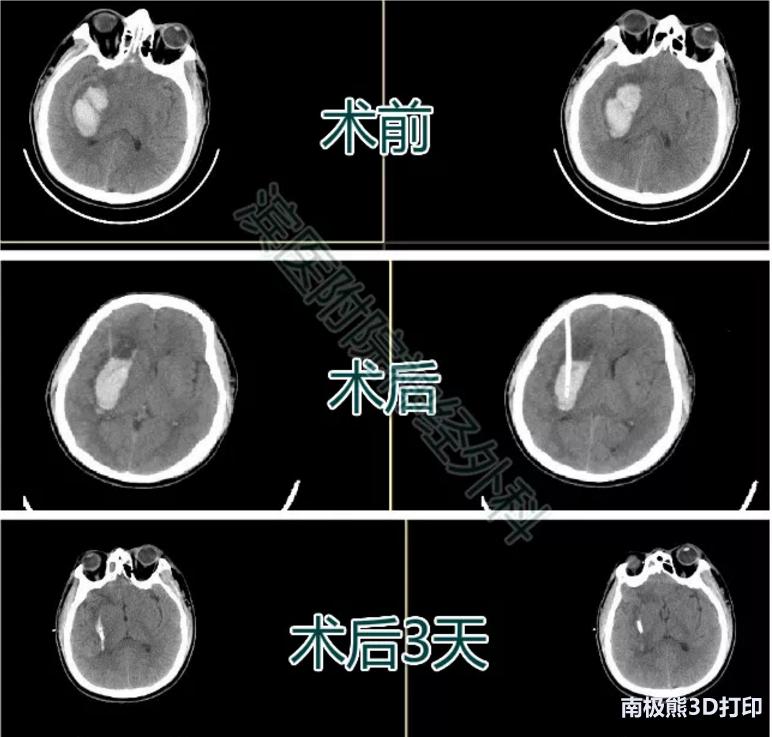

患者张某某,男,50岁,因“突发言语不清伴右侧肢体活动不利6小时”入院。

入院查体:嗜睡状态,呼喊睁眼,言语不清。双侧瞳孔直径约2mm,对光反应迟钝。右侧肢体肌力2级 ,左侧肢体5级。颅脑CT示左侧基底节区脑出血。入院后排除手术禁忌,行3D导板下经额部血肿腔穿刺术,术后复查颅脑CT如图,引流管位于血肿腔中心,穿刺位置满意。术后17天复查颅脑CT示血肿完全吸收,右下肢肌力4+,右上肢肌力4级。生活自理。

患者三影像资料

患者王某某,男,46岁,因“头痛伴左侧肢体活动不灵3天”入院。

入院查体:嗜睡状态,呼叫睁眼,言语尚可。双侧瞳孔直径约2mm,对光反应存在。左侧肢体肌力2级 ,右侧肢体肌力5级。颅脑CT示右侧基底节区脑出血。入院后排除手术禁忌,行3D导板下经额部血肿腔穿刺术,术后复查颅脑CT如图,引流管位于血肿腔中心,穿刺位置满意。辅以尿激酶血肿腔注入术后3天复查血肿已基本没有。

患者四影像资料